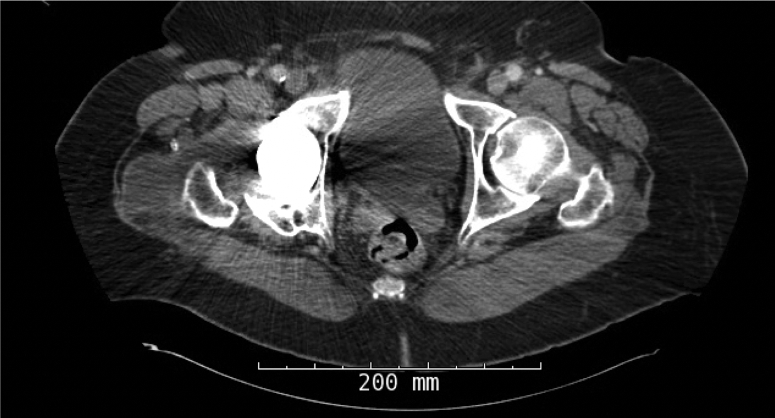

Figure 3.

Axial CT scan demonstrating periprosthetic fluid collection.